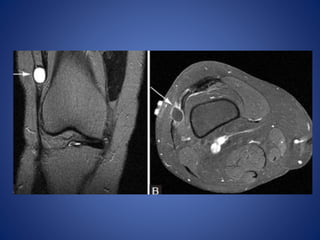

• #7 Popliteal cyst. (A) radiograph demonstrates coarse calcifications (arrow) in the popliteal fossa. (B) USG image at the level of popliteal fossa demonstrates a cystic lesion containing echogenic calcifications (arrow) with posterior acoustic shadowing. (C) Axial T2W image through right knee demonstrates the hyperintense popliteal cyst fluid arising between semimembranosus (arrowhead) tendon and medial head of gastrocnemius (asterisk), with hypointense loose bodies (arrow) layering dependently

• #9 PTFJ cyst. Axial T1W MR image (A) demonstrates uniformly hypointense mass (arrow) with small tail (arrowhead), arising from proximal tibiofibular joint. Lesion (arrow) is hyperintense on STIR (B) and does not enhance on post-contrast T1W fat-saturated image